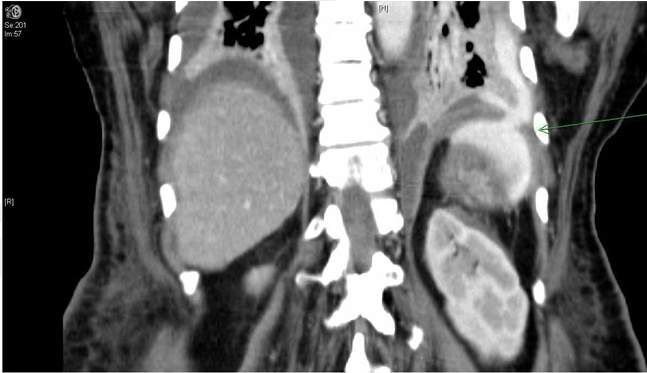

On day-10 postoperatively, the patient started complaining of abdominal pain, her heart rate was increasing up to 130 bpm, as well as her respiratory rate 25/min, and she had fever reached 38.5°C. The patient was transferred to the ICU then, intubated and sedated; work-up done to diagnosis sepsis. The patient was started on empirical IV antibiotics. Chest X-ray was done and revealed pleural effusion for which a pig tail catheter was inserted. The drainage fluid was pus and sent for culture and sensitivity (Figure 1). The patient condition did not improve in spite of the drainage of empyema. Computed tomography scan of chest, abdomen and pelvis showed gastropleural fistula (Figure 2). The patient was taken immediately for an exploratory laparotomy. The stomach was dissected from the diaphragm and it came out very easily. Then by close inspection, a tiny hole on the greater curvature was found and closed. Also the hole in the diaphragm was identified and closed. Postoperatively, the patient was transferred back to the ICU for stabilization, and then transferred to the surgical ward. She was stable, no fever, tolerating oral feeding. Computed tomography scan of abdomen and chest was normal. The drains were removed and the patient was discharged home in a good condition.

Figure 2: Computed tomography scan showing gastric perforation with contrast extravasation extending between pleural cavity and peritoneum (arrow).